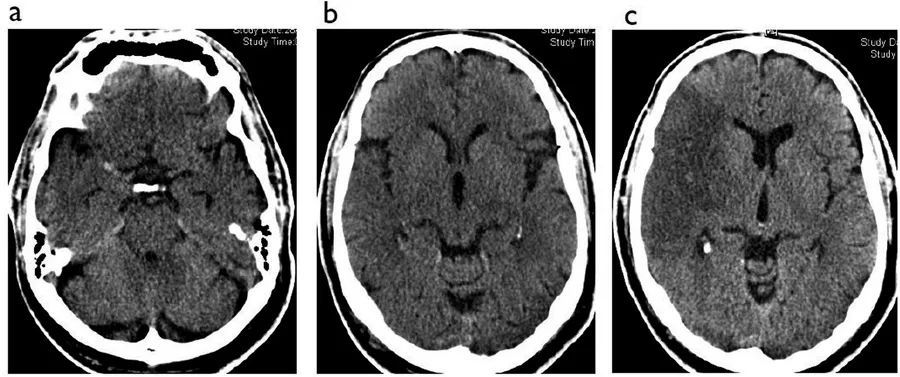

例5

图5  60岁男性,缺血性脑卒中超急性期,A~B:发作后2小时CT;C:发病3天后CT

本例患者右侧大脑中动脉M1段可见高密度影,大脑中动脉供血区超过1/3的区域出现了低密度的早期缺血改变。本例患者接受了静脉溶栓治疗,但没有从中获益。

3天后患者的CT扫描确定了右侧大脑中动脉供血区的梗死。此时病灶更加清晰易见,病灶密度更低、边界更清晰,并有轻微的占位效应,大脑外侧裂消失。占位效应通常在发病后3~5天最为明显,很少非常大,但有时可能与脑疝相关。脑水肿在发病第一周后开始减轻,通常在12~21天后消退。